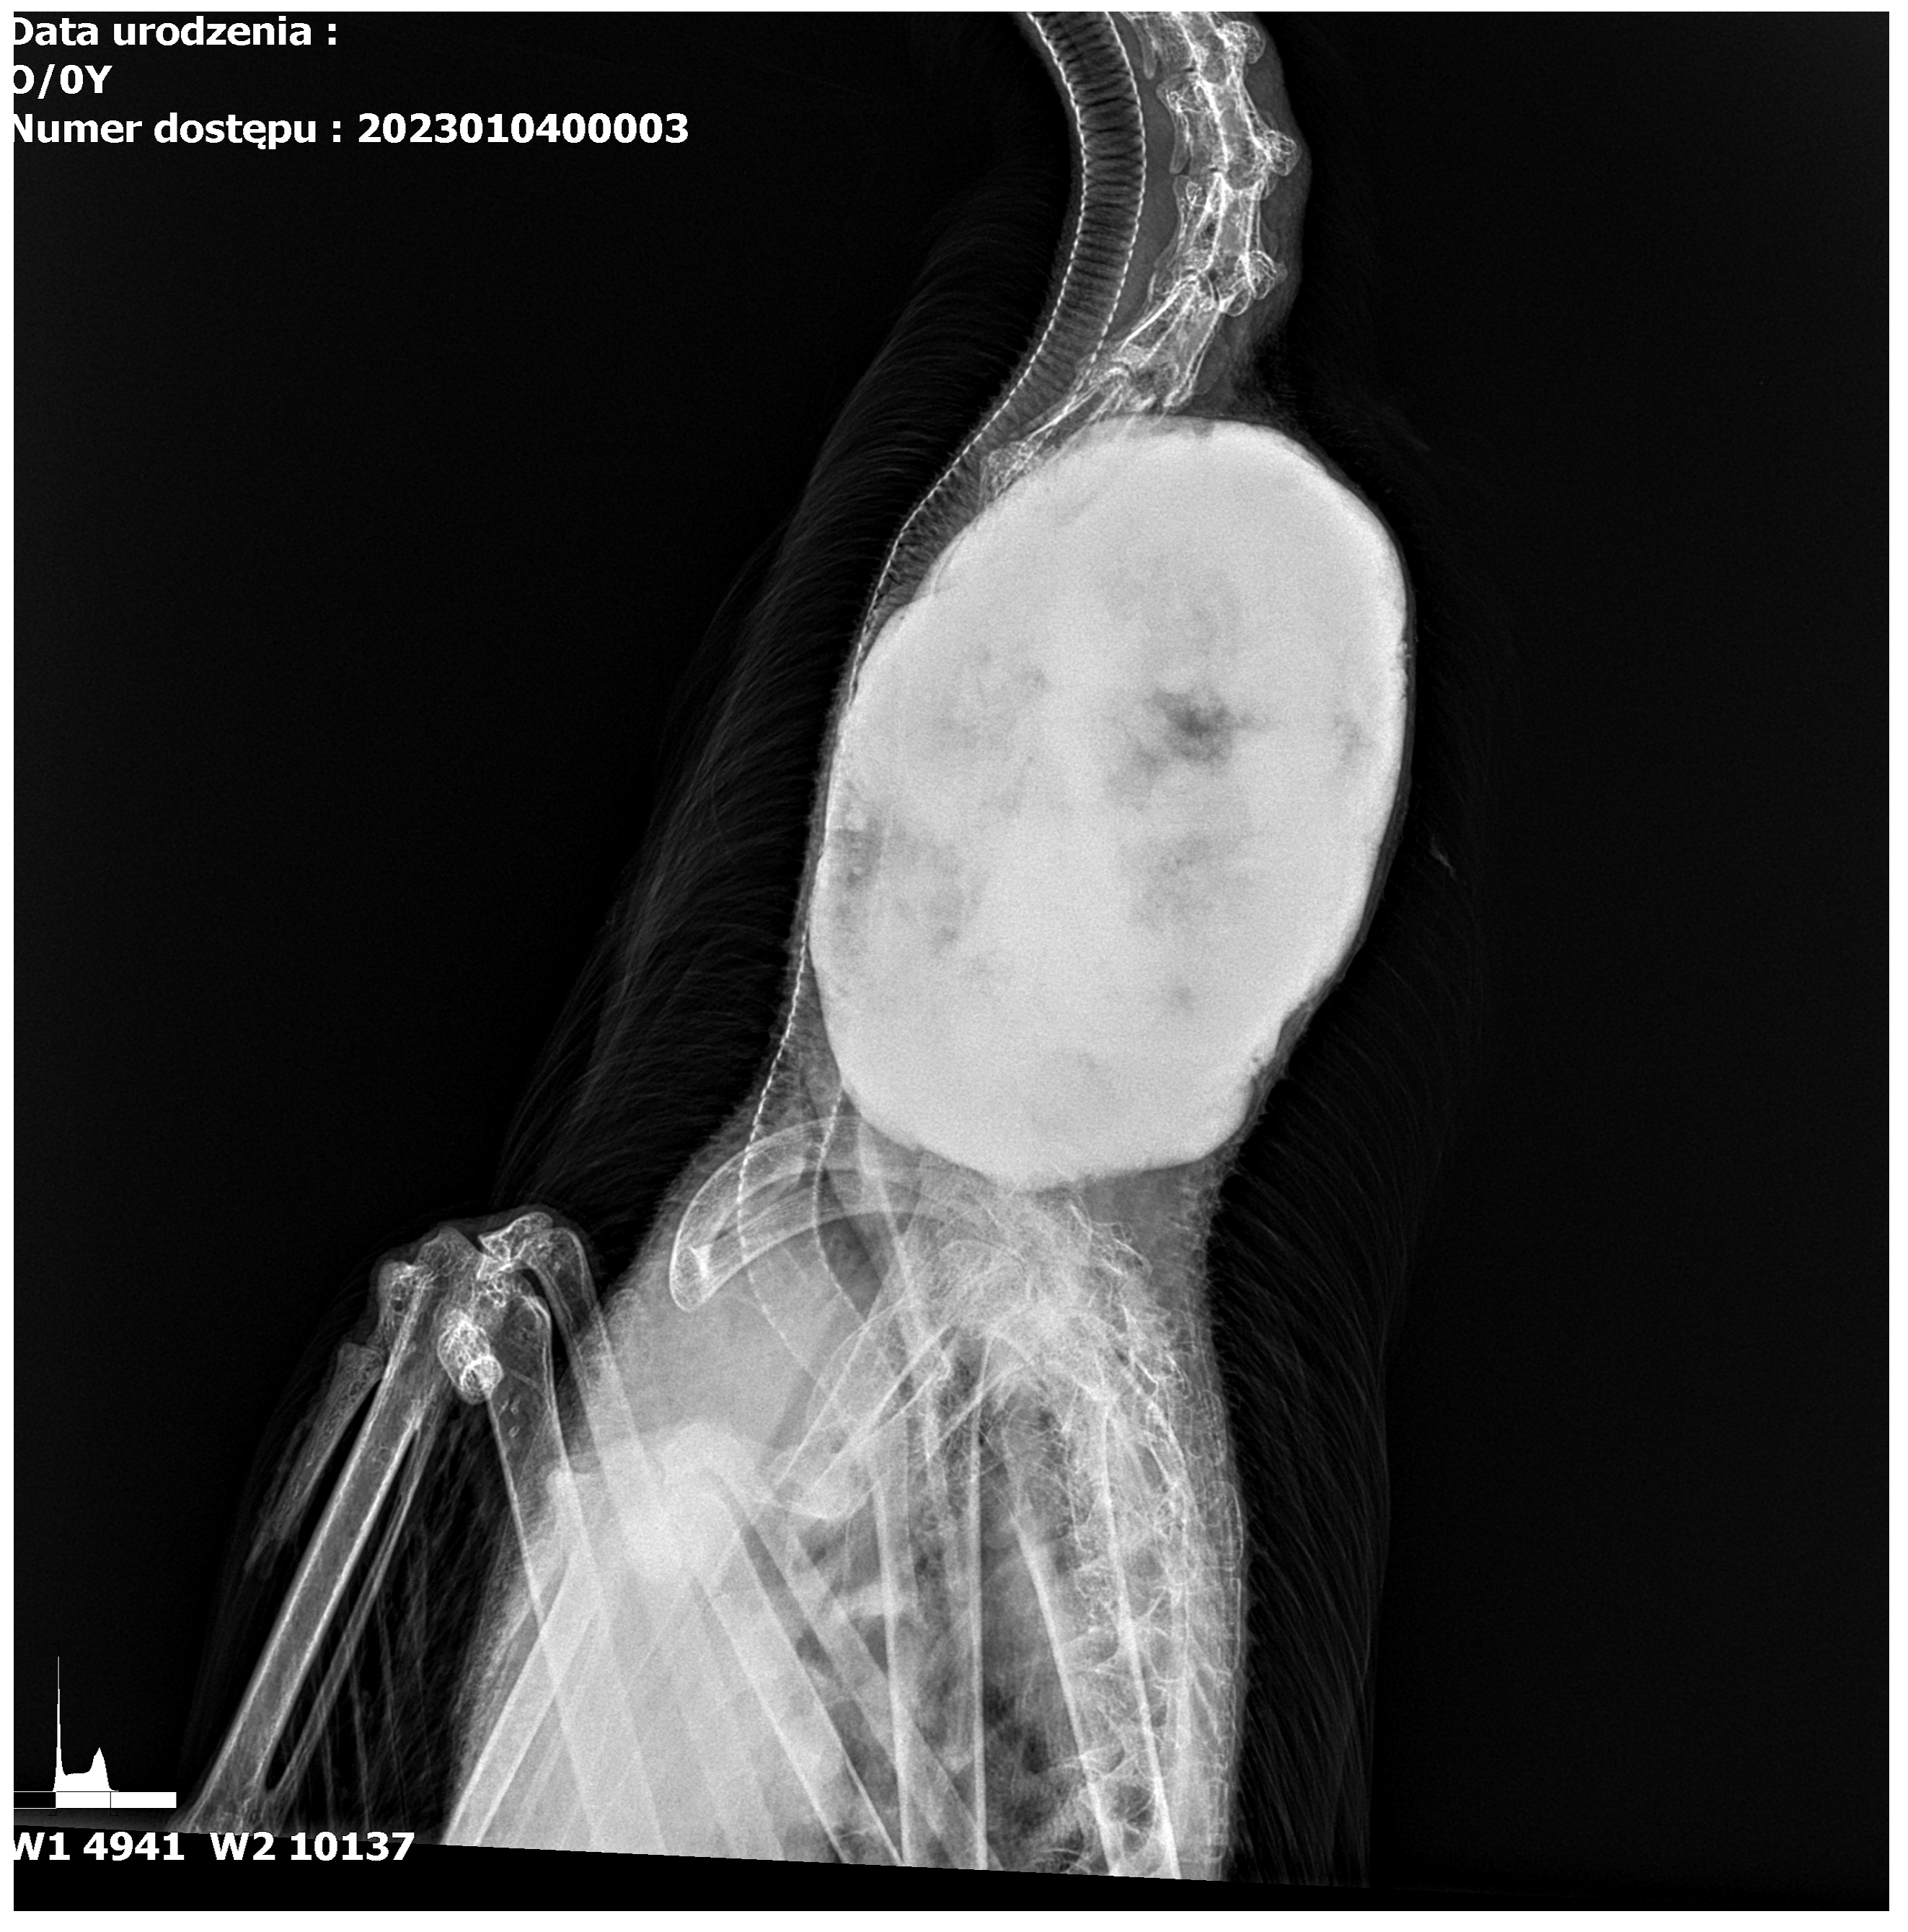

The radiograph examination was taken in two projections, dorsal and lateral (Figure 1 and Figure 2) and in the area of the 8-13 cervical vertebra, a osseous change with the involvement of other cervical vertebrae was noted. The change was a well-circumscribed hyperechogenic mass extending into the thoracic cavity. A tumour measuring 15 cm in length and 10 cm in width was dense and had well-defined borders, suggesting the presence of calcified bone tissue. The tumour was spherical with a homogeneous surface, indicating slow and mild growth. It showed the signs of calcification without causing visible destruction of the surrounding soft tissues and adjacent structures. The tumour slightly pushed the trachea and oesophagus at the sides of the neck but did not affect their patency.

Figure 2. Lateral radiograph of the cervical region in goose. The tumour has pushed the trachea to the sides of the neck without altering its patency.